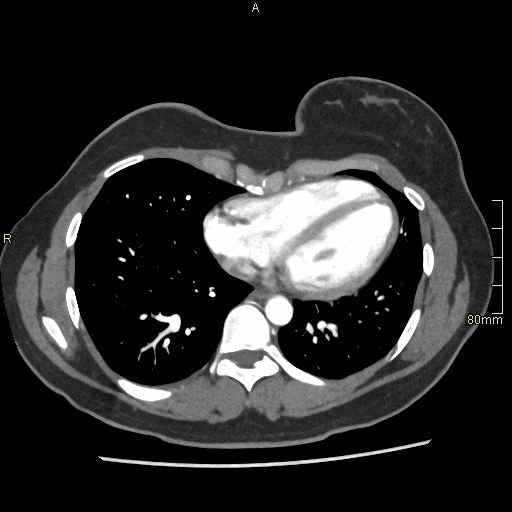

CT Angiography Renal - Maximum Intensity Projection (axial)

CT Angiography Renal - Subtraction (axial)